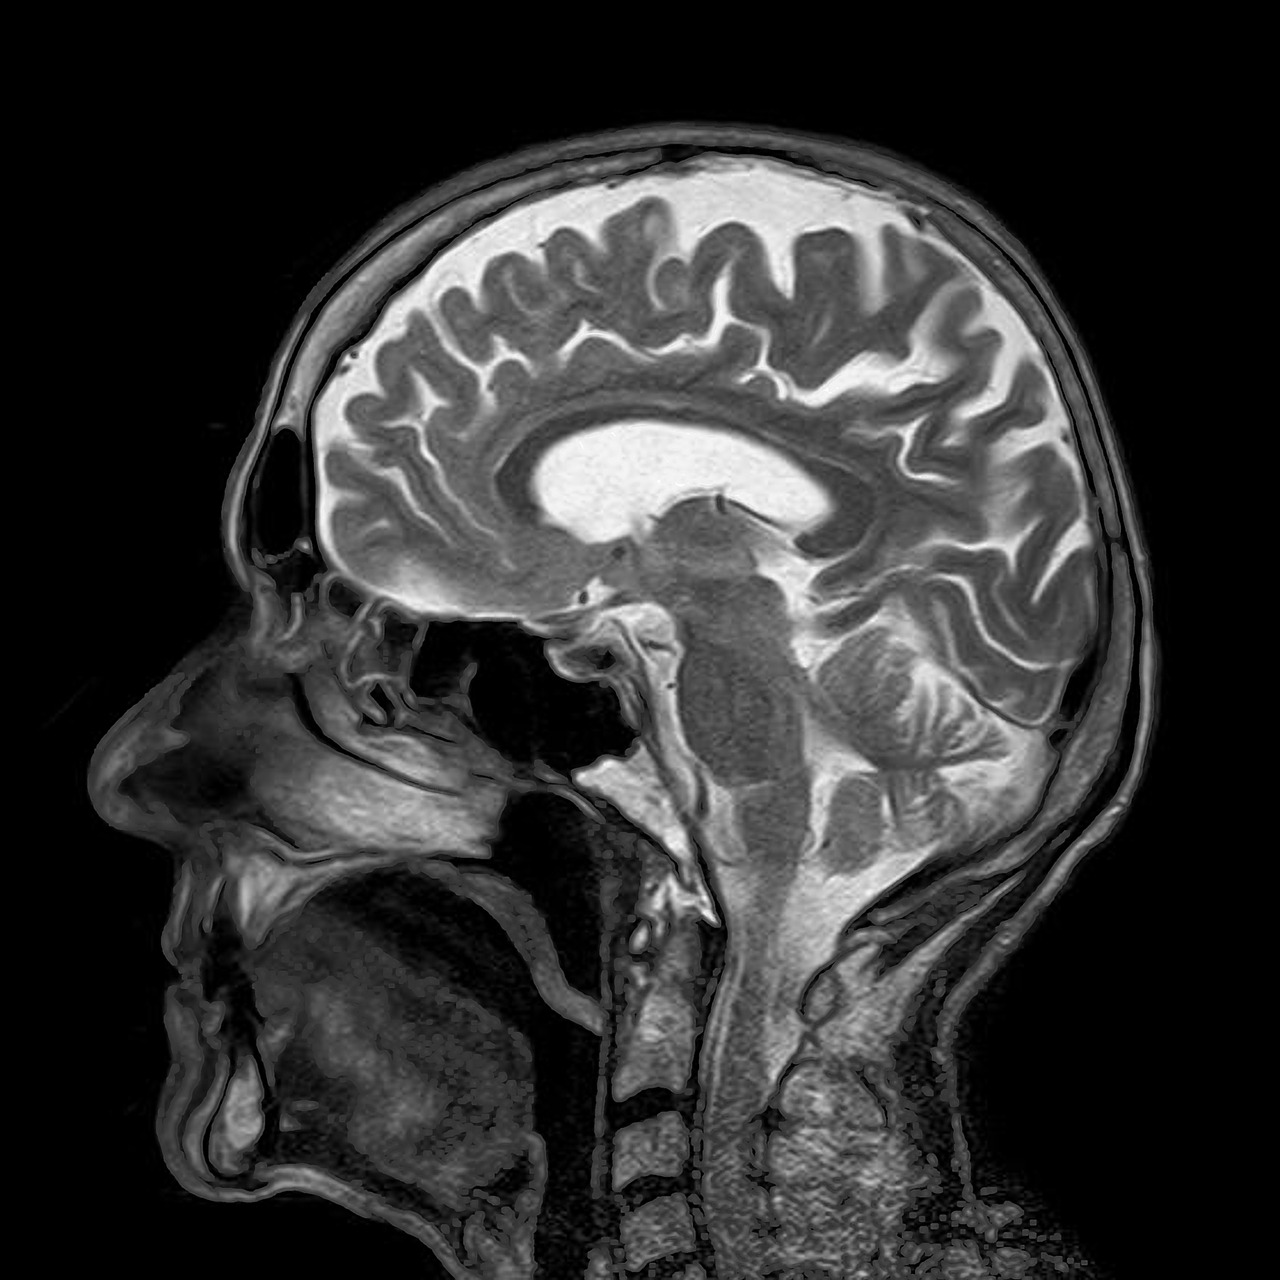

Como funciona e suas vantagens na análise de exames a distância:

A telerradiologia é um serviço inovador que revoluciona a forma como os exames radiológicos são analisados e laudados.

Diferentemente do processo tradicional, onde o exame é realizado e laudado no mesmo local, a telerradiologia permite a execução do exame localmente, seja em clínicas, hospitais ou centros de diagnóstico, enquanto o laudo é emitido remotamente por uma equipe de especialistas em radiologia.